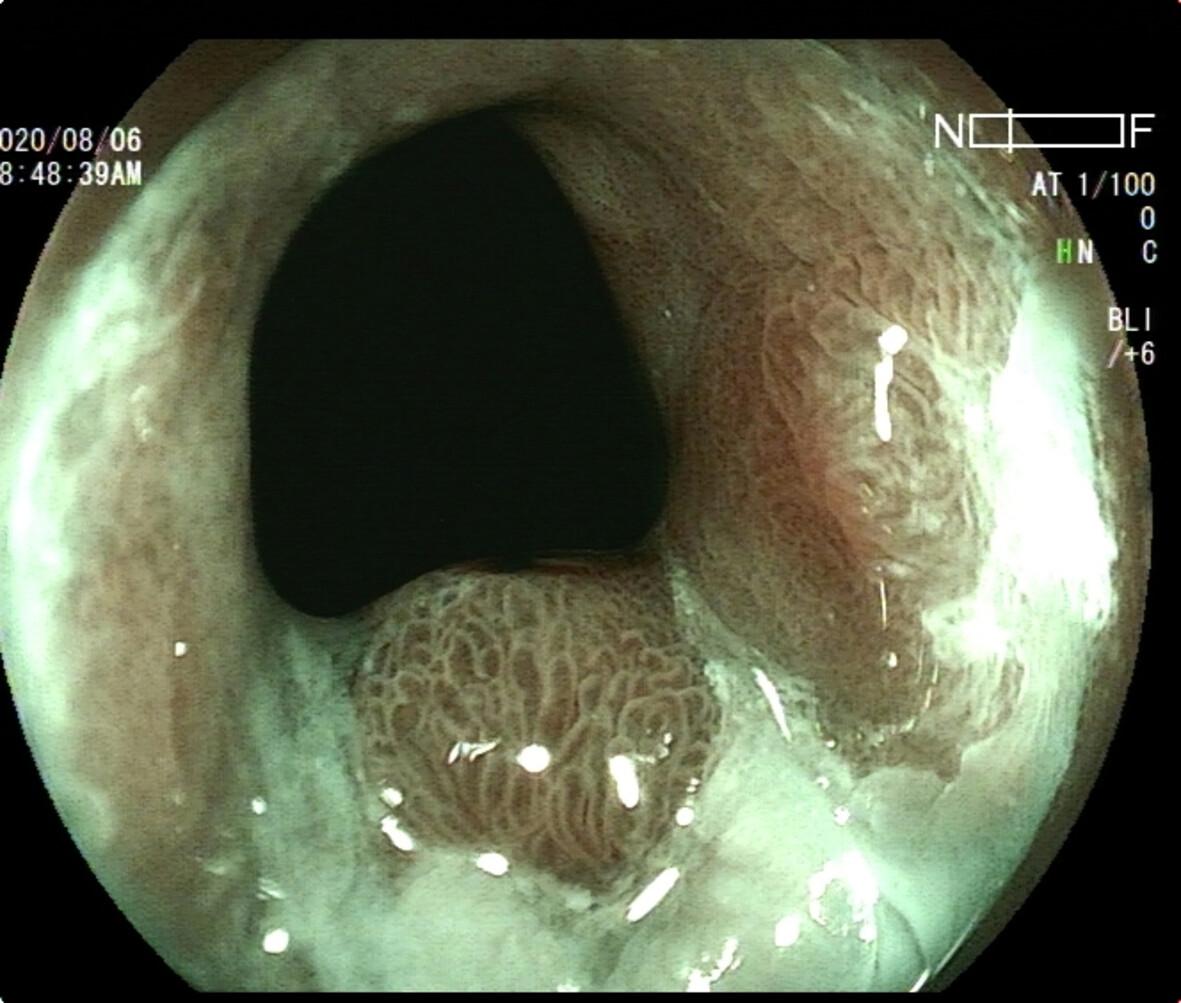

The detection rate of cardia polyps in the BLI group was higher than that in the WLI group (7.87% vs 4.22%, P = 0.018). The rate of overlooked lesions in the BLI group was lower than in the WLI group (0.64% vs 3.38%, P = 0.003). The diagnostic coincidence rate between magnifying BLI and histopathology was 88.16%. The sensitivity, specificity, positive predictive value and negative predictive value for the diagnosis of neoplastic lesions by magnifying endoscopy with BLI were 90.91%, 87.69%, 55.56%, and 98.28%, respectively. The most remarkable patterns for predicting inflammatory polyps were the prolonged and fine network patterns (sensitivity 71.43%, specificity 93.75%). Small round combined with honeycomb patterns were the most common among fundic gland polyps (sensitivity 80.00%, specificity 98.48%). Neoplastic lesions presented as villous or ridge-like combined with core vascular or unclear pattern for both microvascular and microstructure patterns.

Abstract Image